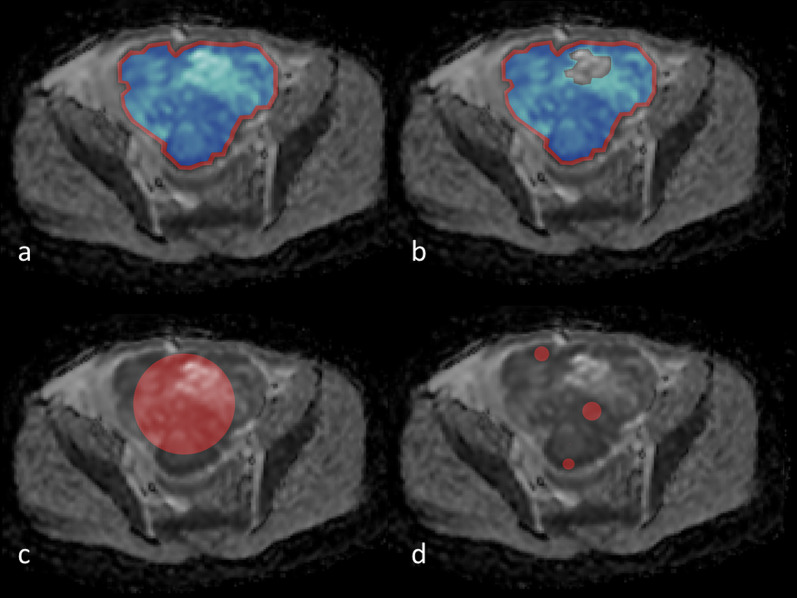

An example of these strategies is given in Fig. 2.

Fig. 2.

Illustrative example of diffusion-weighted image with regions of interest (ROIs) of six commonly used segmentation areas highlighted. a ‘Inside’ strategy, blue area. ‘Whole tumor’ strategy, red + blue area. b ‘Inside solid’ strategy, blue area. ‘Solid’ strategy, red + blue area. c ‘Circle’ strategy. d ‘Max DWI circles’ strategy